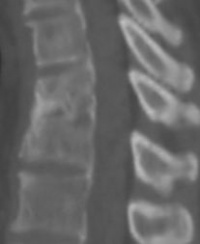

图片说明:左图为治疗前二维CT,右图为微创治疗后3年半

随访二维CT照片。